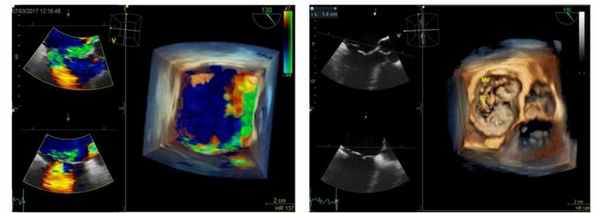

На основании дооперационной трансторакальной эхокардиографии планировалась имплантация опорного кольца и коррекция пролапса ПМС за счёт имплантации неохорд или транслокации хорд от задней митральной створки к передней. Данные интраоперационной трёхмерной ЧП ЭхоКГ позволили визуализировать расщепление передней створки митрального клапана и подтвердить дилатацию фиброзного кольца. Таким образом, тактика операции была изменена и выполнена пластика расщеплённой передней створки МК, имплантация опорного кольца Carpantier-Edwards №32, пластика трикуспидального клапана по de Vega.

После отключения искусственного кровообращения и стабилизации гемодинамики выполнено контрольное ЧП ЭхоКГ исследование. Показатели функционального состояния миокарда, клапанного аппарата были в норме.

В представленном клиническом случае больной с патологией митрального клапана – выраженной недостаточностью, в плановом порядке интраоперационно до основного этапа операции проведена чреспищеводная эхокардиография с построением в режиме реального времени трёхмерной модели клапана, позволившая детально оценить патологию и определить механизм формирования митральной недостаточности. С помощью трёхмерной реконструкции удалось диагностировать расщепление передней створки митрального клапана, определить точную локализацию патологии.

Полученные данные были подтверждены непосредственно в ходе операции при ревизии клапана и явились основанием выбора тактики хирургического вмешательства.